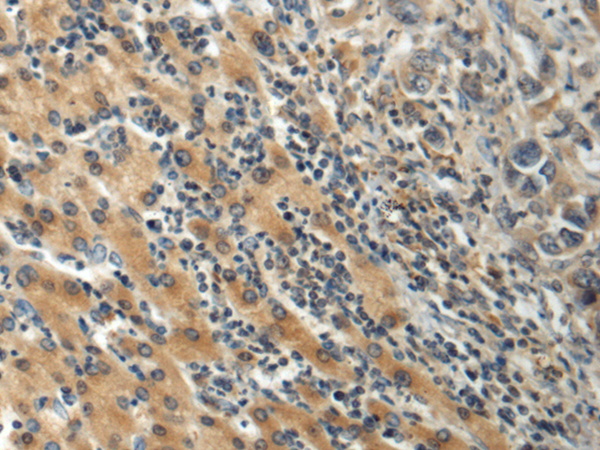

IHC positive control: |

Human liver cancer |

IHC Recommend dilution: |

100-300 |